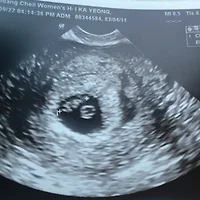

(10/29) 12주 1일 처음 보는 정밀 초음파

시간이 또 훅 가고 만난 건 첫 정밀 초음파!

정말 몇 주 안지났는데 인간의 형태를 완벽하게 갖춘 걸 보고 엄청 놀랐던 기억이 난다..

(느낌은 전혀 없지만) 나름 꼼지락 하기도 하고, 팔다리도 휘젓고, 눕는 방향도 바꾸고, 입도 오물오물하는..

(이런게 모두 초음파로 잡힌다는것도 너무 신기하지 않은가!!)

혹시나 성별을 알 수 있을 수도 있다는 주수인 12주차였지만, 초음파 봐주는 선생님이 매우 꼼꼼하게도 다리 아래는 안보시더라는 ㅋㅋ